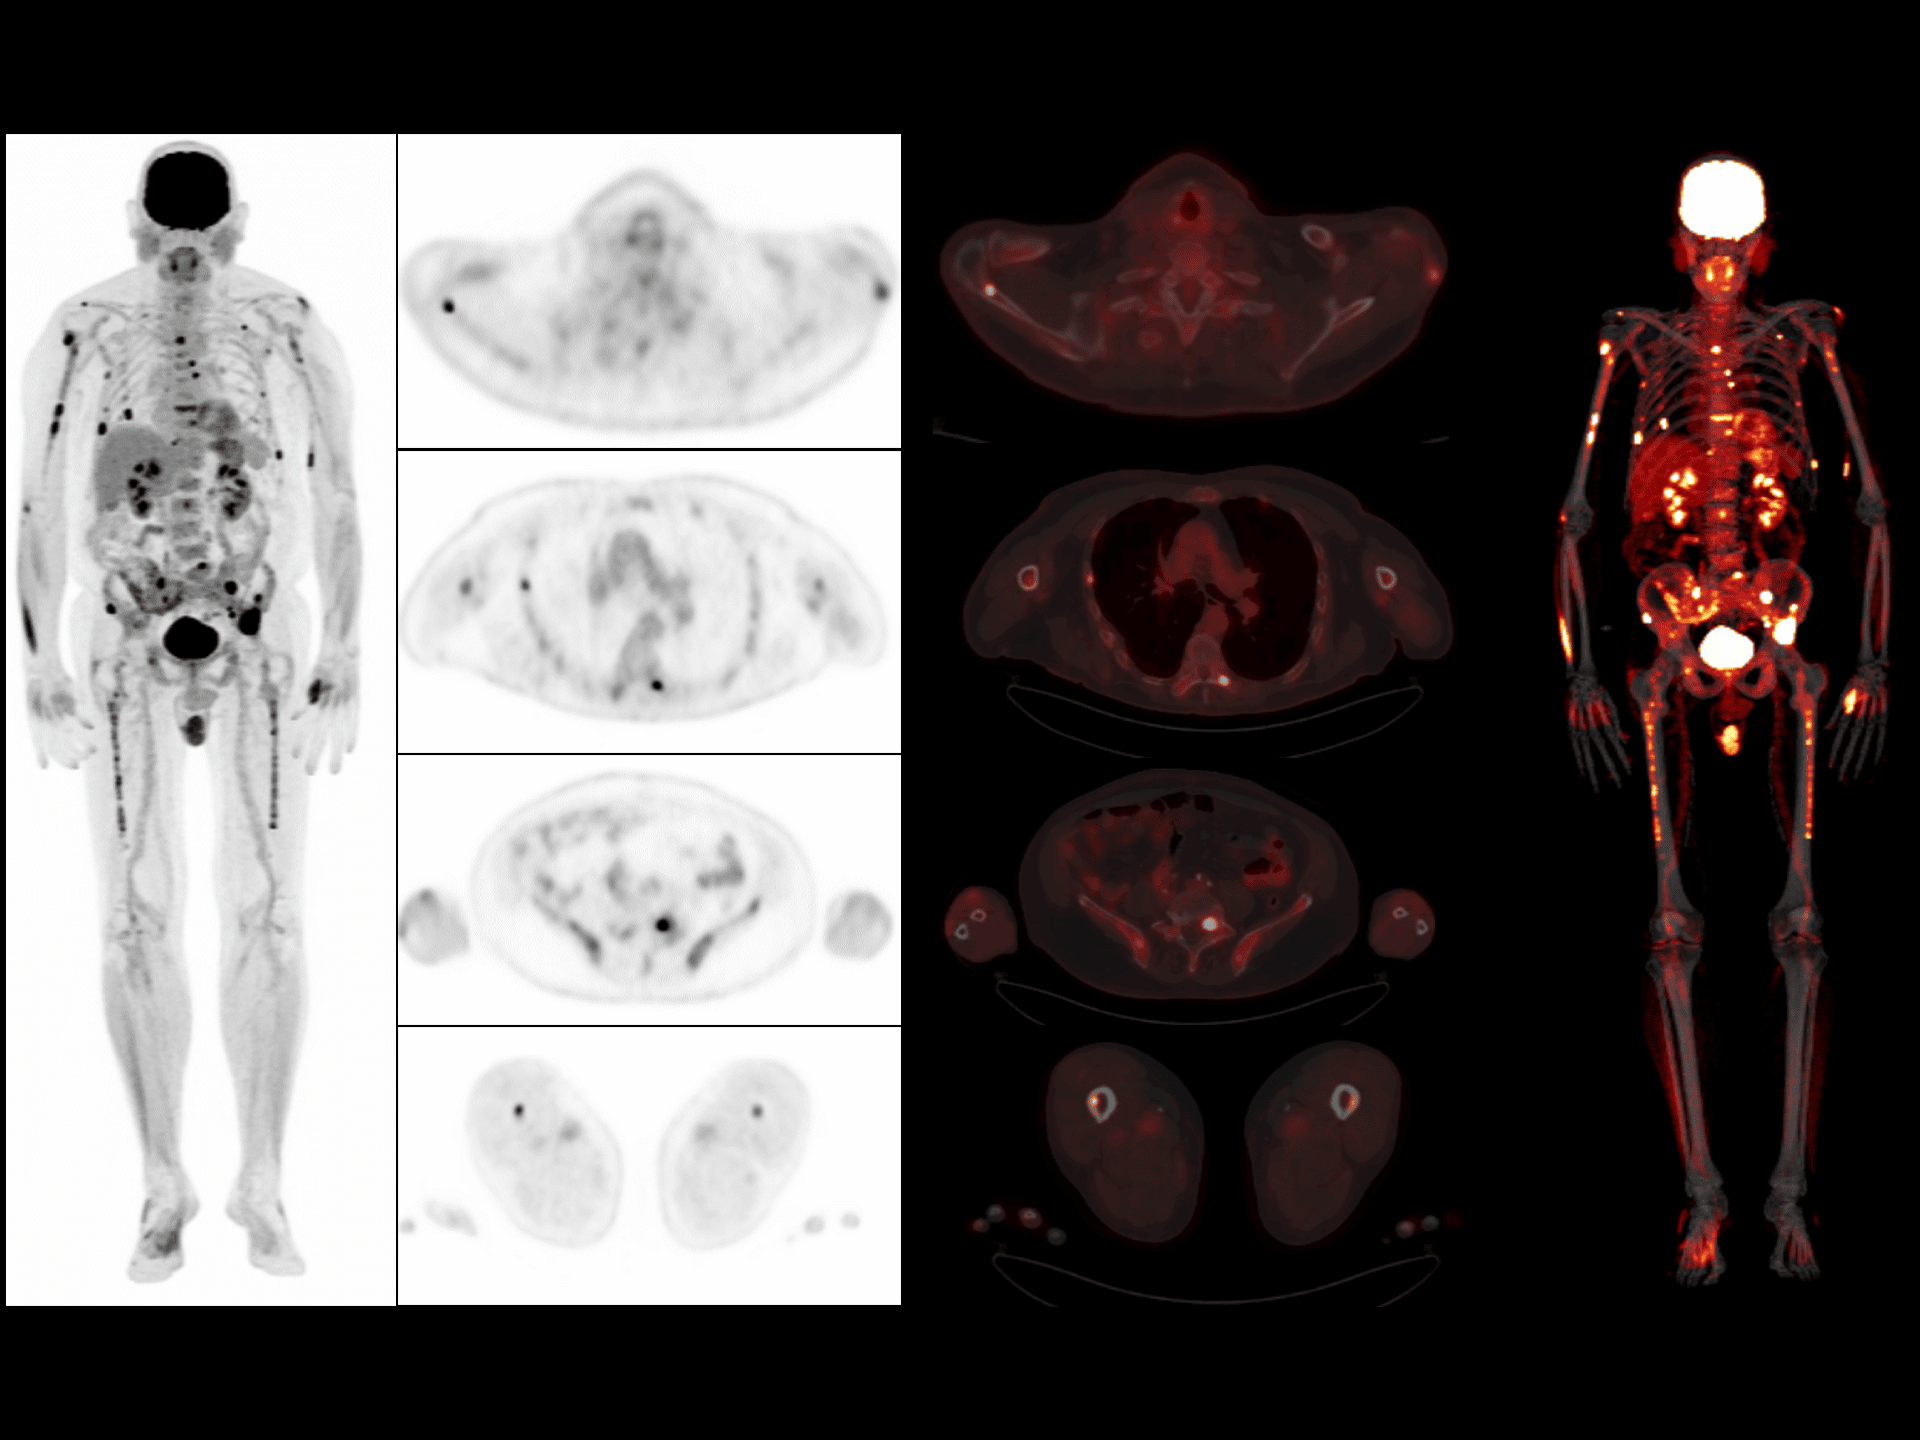

Vizualizare clară a leziunilor în imagistica 68Ga-PSMA

Detectare precisă și contrast superior pentru leziuni în scanările cu radiotrasor 68Ga-PSMA.